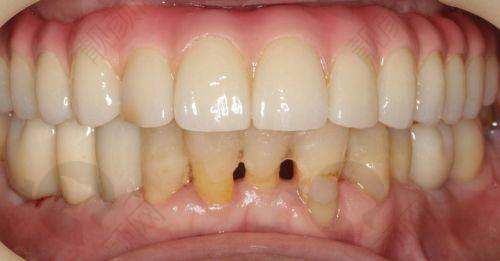

王先生因为骨头条件差,长期缺牙,吃饭都成问题。后来在鼎植口腔做了穿颧种植全口修复,终于能正常吃饭了。他对鼎植口腔的技术和服务都给予了高度评价,觉得鼎植口腔解决了他的大难题。